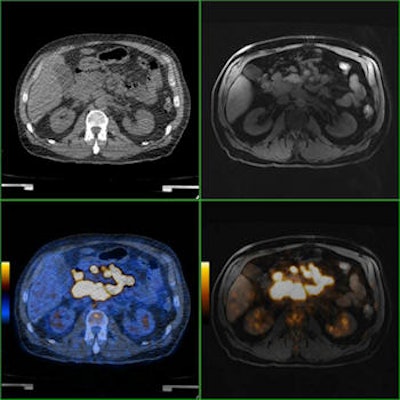

Comparison of PET/CT and PET/MRI of a patient with diffuse large B-cell lymphoma. Axial CT and MRI images show bulky disease in the mesenterium with corresponding 18F-FDG activity in axial PET/CT and PET/MRI. In this patient, lesion conspicuity was rated as "excellently delimitable" for MRI and "good delimitable" for CT. All images courtesy of Dr. Philippe Appenzeller.Even when routine clinical body-coil imaging alone is not adequate to achieve sufficient image quality, there "might be a clinical situation in multimodality imaging where it might be desirable to have a quick whole-body PET/MRI," the authors explained. So, the purpose of their study was to determine the diagnostic utility of a PET/MRI with only an axial T1-weighted fast-gradient-echo sequence using a body coil, which is needed for MRI-based attenuation correction, compared with standard low-dose PET/CT.